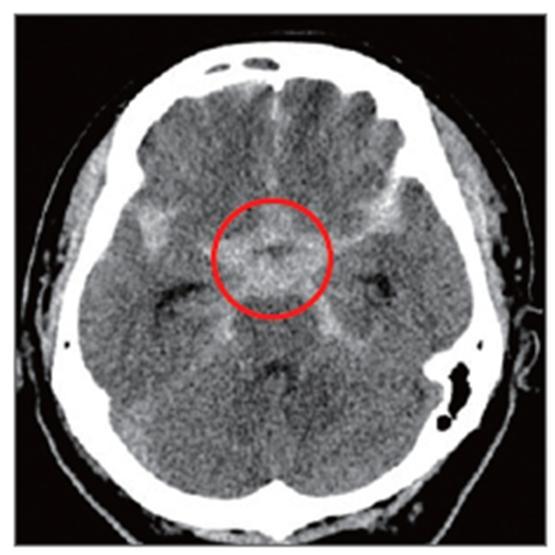

▶뇌동맥류 & 뇌 지주막하 출혈 사진

5_뇌동맥류, 뇌지주막하출혈 사진1.jpg

5_뇌동맥류, 뇌지주막하출혈 사진2.jpg

1. 뇌혈관조영술에서 혈관벽이 풍선처럼 부풀어 오른 뇌동맥류 모습(빨간 원안).

2. 뇌지주막하출혈 뇌CT. 뇌 가운데에 흰색으로 보이는 별모양의 급성 출혈이 보임.